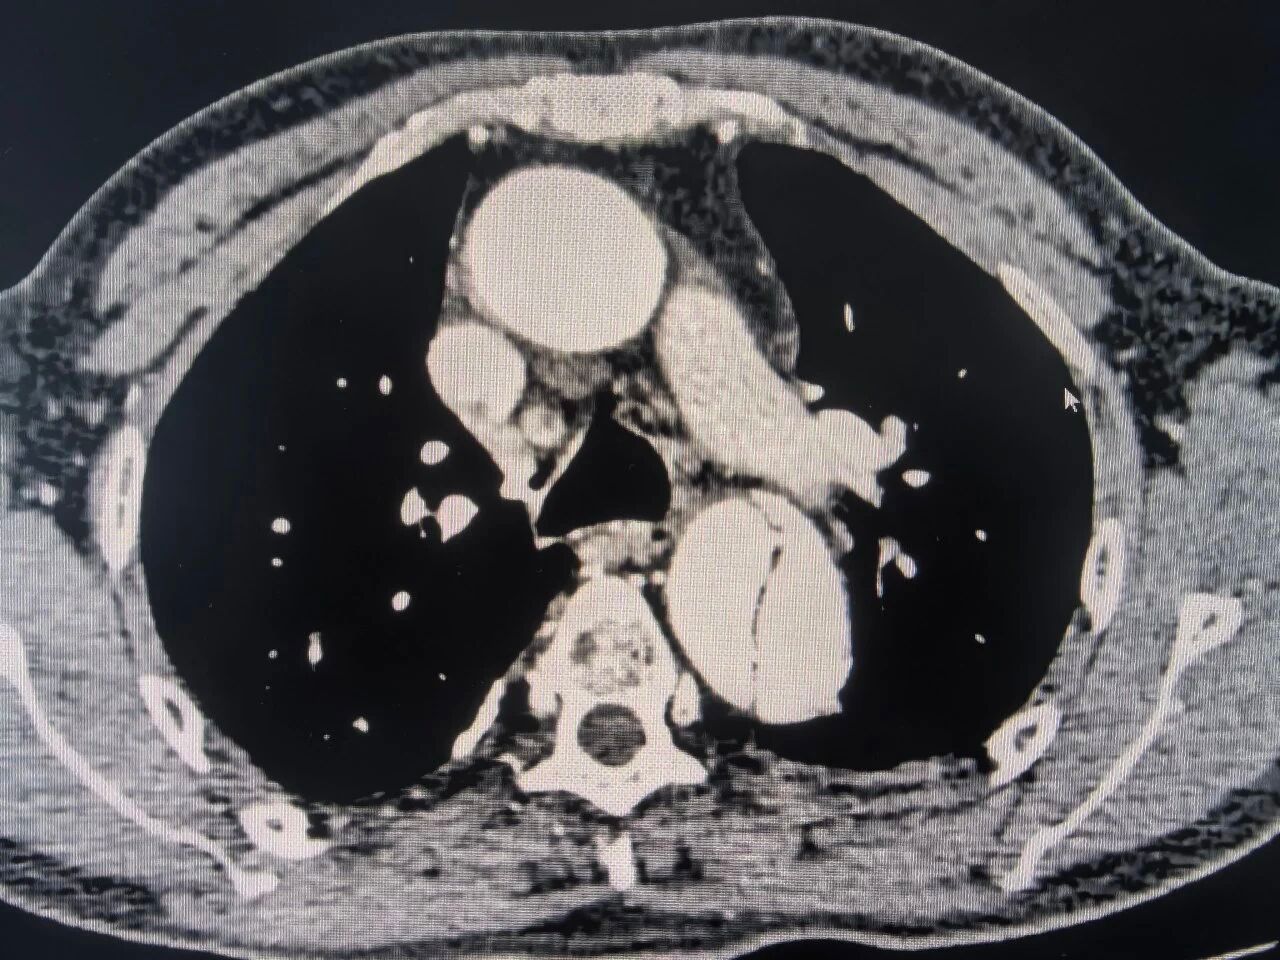

术前CT检查

这是一种极其凶险的血管疾病,主动脉内膜撕裂后,血液涌入血管壁中层,如同在体内形成一个随时可能破裂的“假腔”,一旦夹层破裂,患者将面临致命性大出血,生死只在顷刻之间。

在心胸外科的主导下,介入导管室、麻醉科等多科室专家迅速集结,开展了细致的术前讨论。针对患者病变位置、血管条件以及手术风险,专家团队制定了周密的手术方案“主动脉B型夹层覆膜支架腔内隔绝术”。这是一种微创介入技术,无需开胸,仅通过大腿根部几毫米的穿刺点,将特制的人工血管支架精准输送至病变位置,像“堤坝”一样封堵住内膜破口,恢复血流通畅。